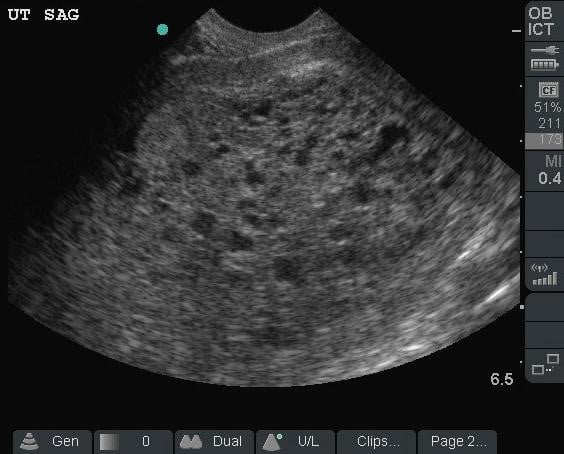

- Illustration 5. Illustration of sagittal approach and relevant anatomy. Probe indicator toward patient’s head (star)

- Illustration 6. Pelvis sagittal view with relevant anatomy